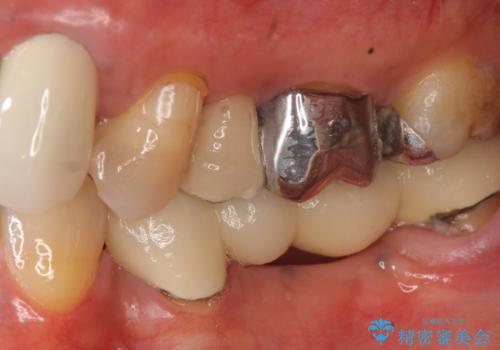

- 昔治療した左上56の延長ブリッジをきちんと治療しなおしたいといらっしゃった方の症例です。

古いブリッジを除去後、オールセラミッククラウンによる補綴を行いました。

- オールセラミッククラウン…¥100,000×3、仮歯…¥10,000×3費用は治療当時の料金となります